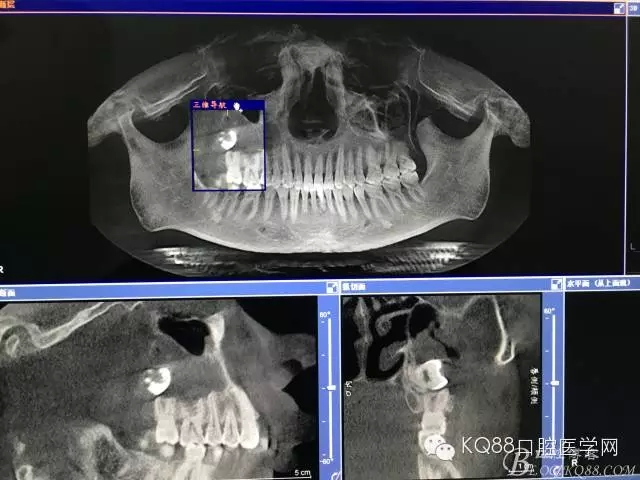

圖3.加拍CBCT影像檢查:18位于上頜竇內(nèi),并導致右側上頜竇粘膜炎性增生。18牙冠的合面朝向頰側。并且與17頰根緊密相鄰。